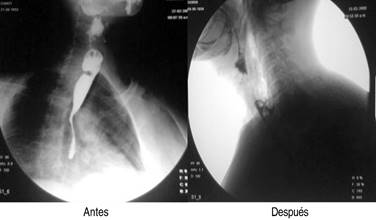

A todos los pacientes se les tomaron datos clínicos demográficos, tales como: edad, sexo, tiempo de evolución de los síntomas y síntomas predominantes, características del divertículo, remisión de los síntomas y necesidad de reintervención. El diagnóstico de divertículo de Zenker se realizó por medio de estudio radiológico de contraste (esofagograma con medio de contraste baritado) y endoscópico, con lo cual se confirmaba el diagnóstico y se calculaba el tamaño del divertículo (Figura 1).

Se realizaron en total 18 procedimientos, se consideró como complicación sólo un paciente (7.1%), quien presentó sangrado importante, mismo que se controló, pero impidió en el procedimiento inicial completar adecuadamente la miotomía, por lo que se reintervino a las 24 horas para completar ésta. Durante los procedimientos, dos pacientes tuvieron enfisema subcutáneo (un paciente femenino de 74 años y uno masculino de 57 años), los cuales fueron tratados de forma conservadora mediante la administración de una cefalosporina de tercera generación, así como control radiográfico para medición del enfisema subcutáneo (Figura 6). No se presentaron complicaciones mayores como mediastinitis, hemorragia incoercible o perforación que requirieran cambiar el tratamiento endoscópico por el quirúrgico de urgencia o programado. La mejoría de la disfagia en todos los casos fue inmediata y en las consultas subsecuentes refirieron haber aumentado de peso, además se realizó endoscopia y trago de material de control (Figura 7).